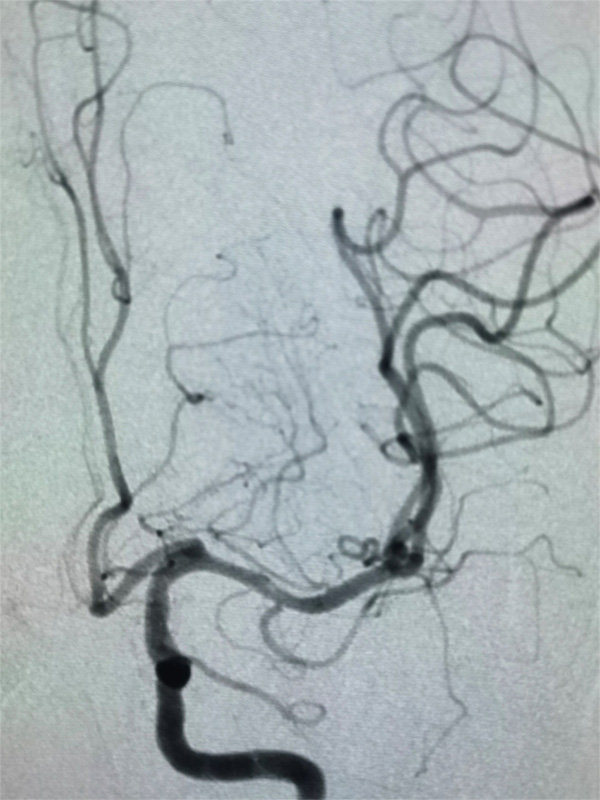

22:30,手术准时开始。柴尔青教授现场指导,巴特尔医生和沈寻医生迅速消毒、铺台、穿刺、接造影导管。术中判断患者是2型主动脉弓,血管硬化严重,超选左侧颈动脉,清楚的显示了病灶,左侧大脑中动脉的闭塞,这需要全麻下才能完成进一步的取栓操作,并且要求麻醉过程中血压要维持在140/80mmHg左右。技术娴熟的麻醉师给药、插管、麻醉,15分钟完成了全部操作,而且血压完全平稳没有波动。

时间一分一秒地飞过,手术按方案顺利推进。取栓导管顺利的通过闭塞血管,取栓支架释放后即带出来了血栓。即刻造影,左侧大脑中动脉血流恢复,远端血管显影,由此发现了发病病因是左大脑中动脉的斑块形成造成管腔重度狭窄(狭窄约99%)后,小血栓的形成又突然把血管完全堵死了,如果不处理血管狭窄,此处会再次发生闭塞,紧急启动备用方案---球扩血管成型,将大脑中动脉狭窄程度缓解了80%左右,瞬间血流完全通畅了,继续观察半小时左右,血流很稳定,宣布手术结束。这时时钟显示为凌晨01:35。从发病到入院,到罪犯血管开通,全程仅仅4个半小时。参与手术的所有医护人员,打赢了这场漂亮的攻坚战。可以很自信地说,在国际标准的溶栓时间窗内顺利完成了颅内血管取栓和开通任务,这也真实体现出了国家应急医学研究中心卒中团队的救治效率和临床经验。

大脑中动脉急性闭塞和血流中断

大脑中动脉术后完全开通以及脑血流恢复